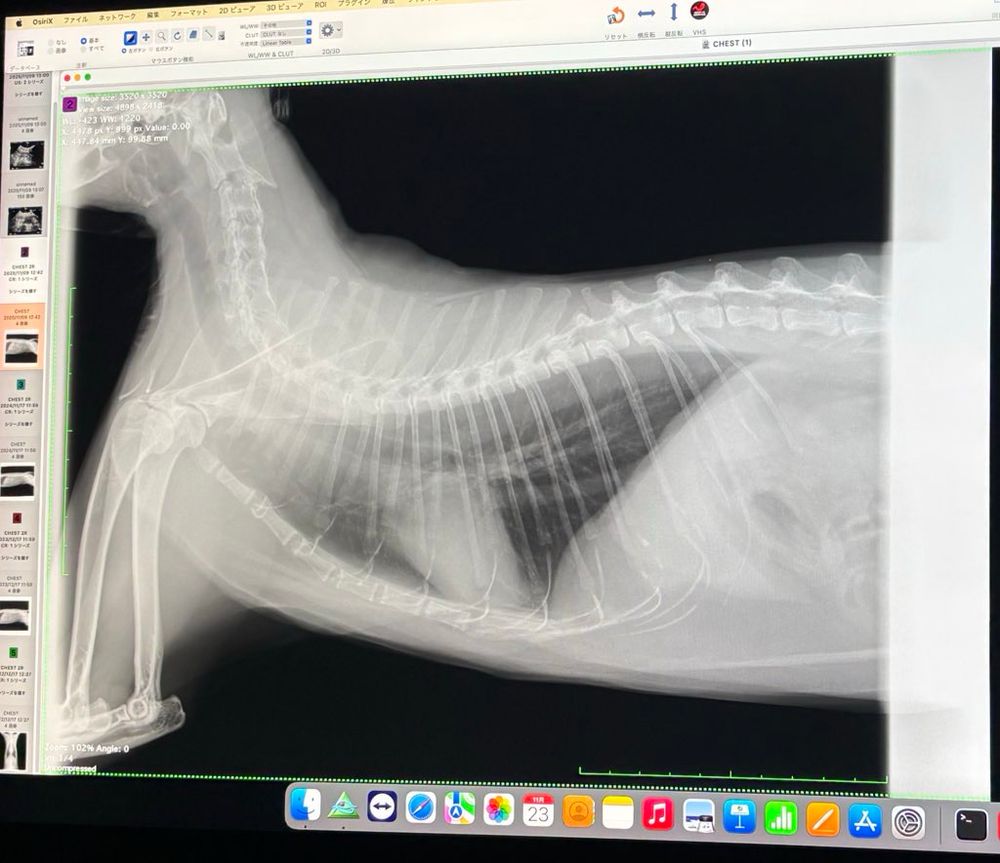

猫さんの健康診断結果聞きに行く。

今年も特に問題なく、健康でした。

骨まで可愛い。